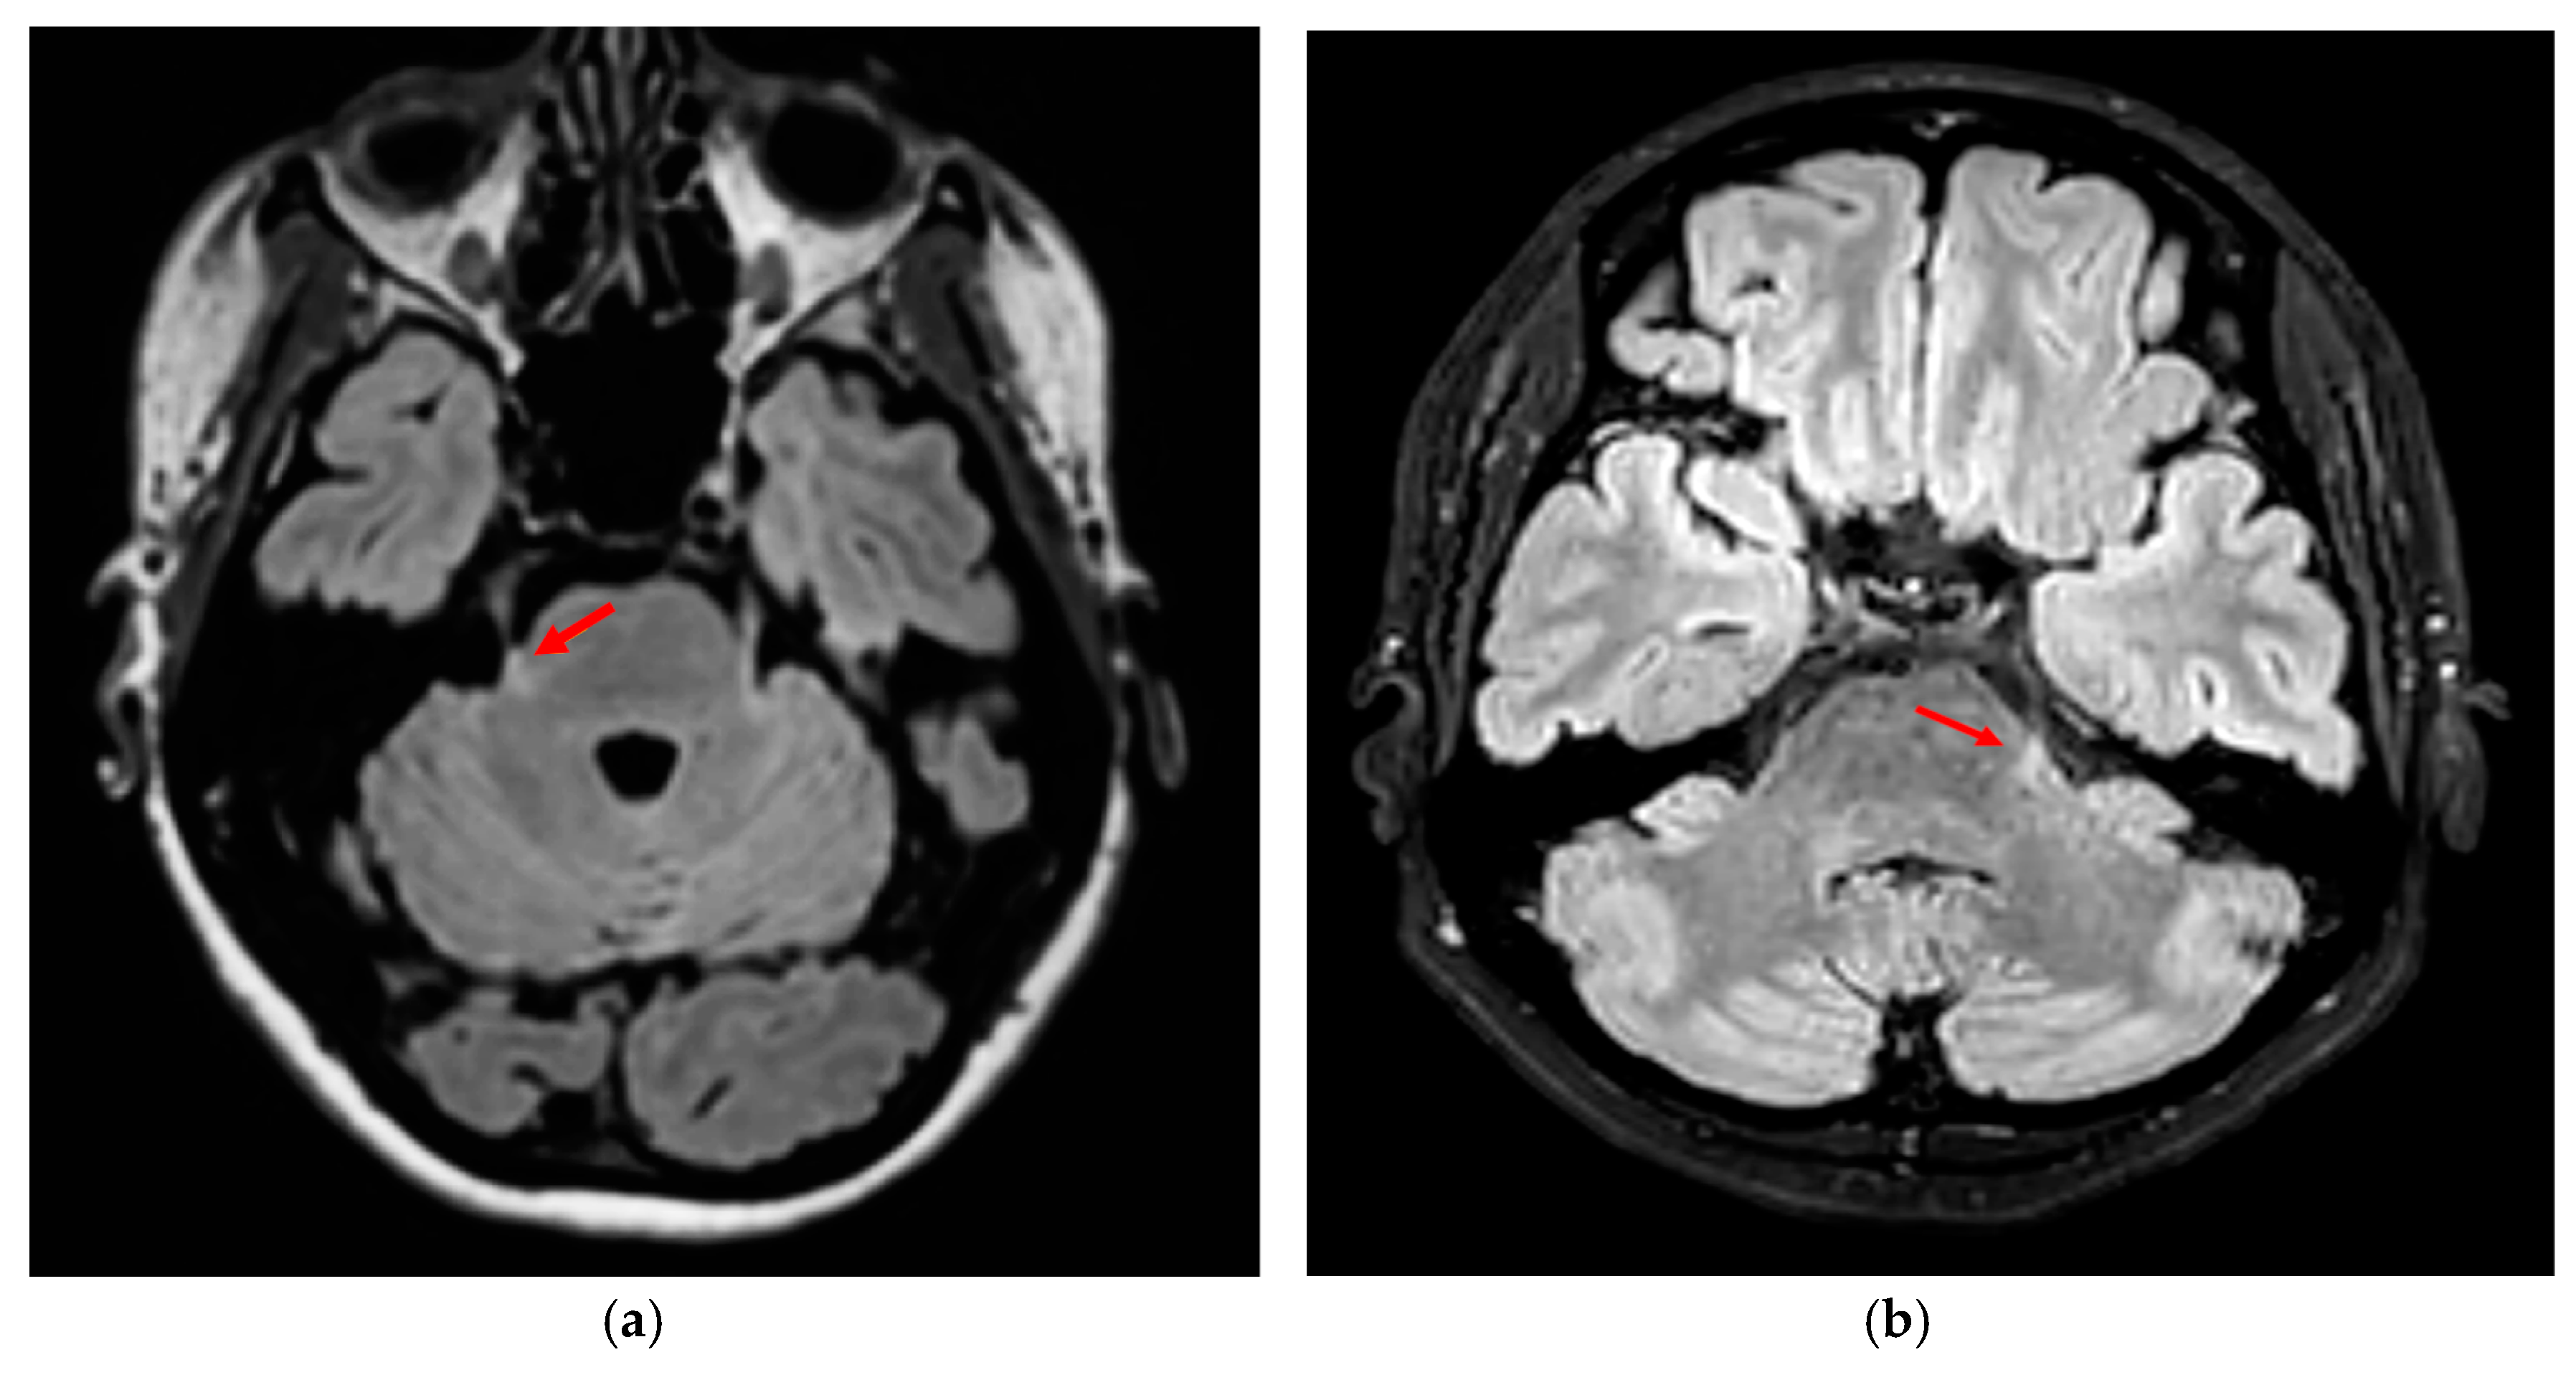

- Demyelinating lesions in strategic brain (stem) regions could trigger or worsen migraine headache in pwMS. The periaqueductal grey matter (PAG) has often been implicated, with three MS cases presenting severe, migraine-like headache alongside PAG lesions on magnetic resonance imaging (MRI), including one with contrast enhancement [26,27]. Gee et al. further supported this link, finding that pwMS with PAG lesions had a significantly higher risk of migraine-like headache (OR 3.91) compared to those without such lesions [28]. Mrabet et al. (2022) also described a predominance of brainstem inflammatory lesions on MRI in pwMS with migraines [29]. Tortorella et al. found more lesions in the substantia nigra and red nucleus in pwMS with migraine but no difference in PAG lesions [30]. Similarly, Papadopoulou et al. found no PAG–migraine association in a retrospective analysis of 250 pwMS [31]. Kister et al. also found no difference in the number of T2 or brainstem lesions between pwMS with and without migraines, although smaller regions like the PAG were not specifically analyzed [32];